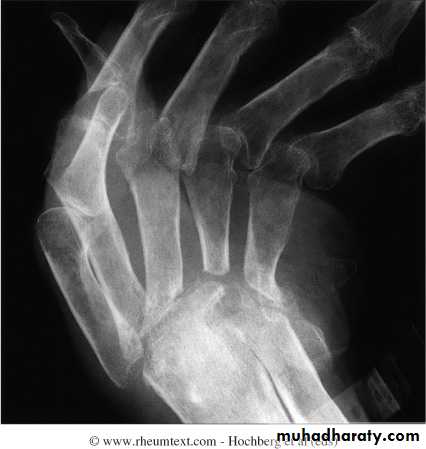

Rheumatoid wrist: articular destruction, carpal fusion and carpal collapse.

Severe destruction of the distal radius and ulna.Atlanto-axial subluxation in RA